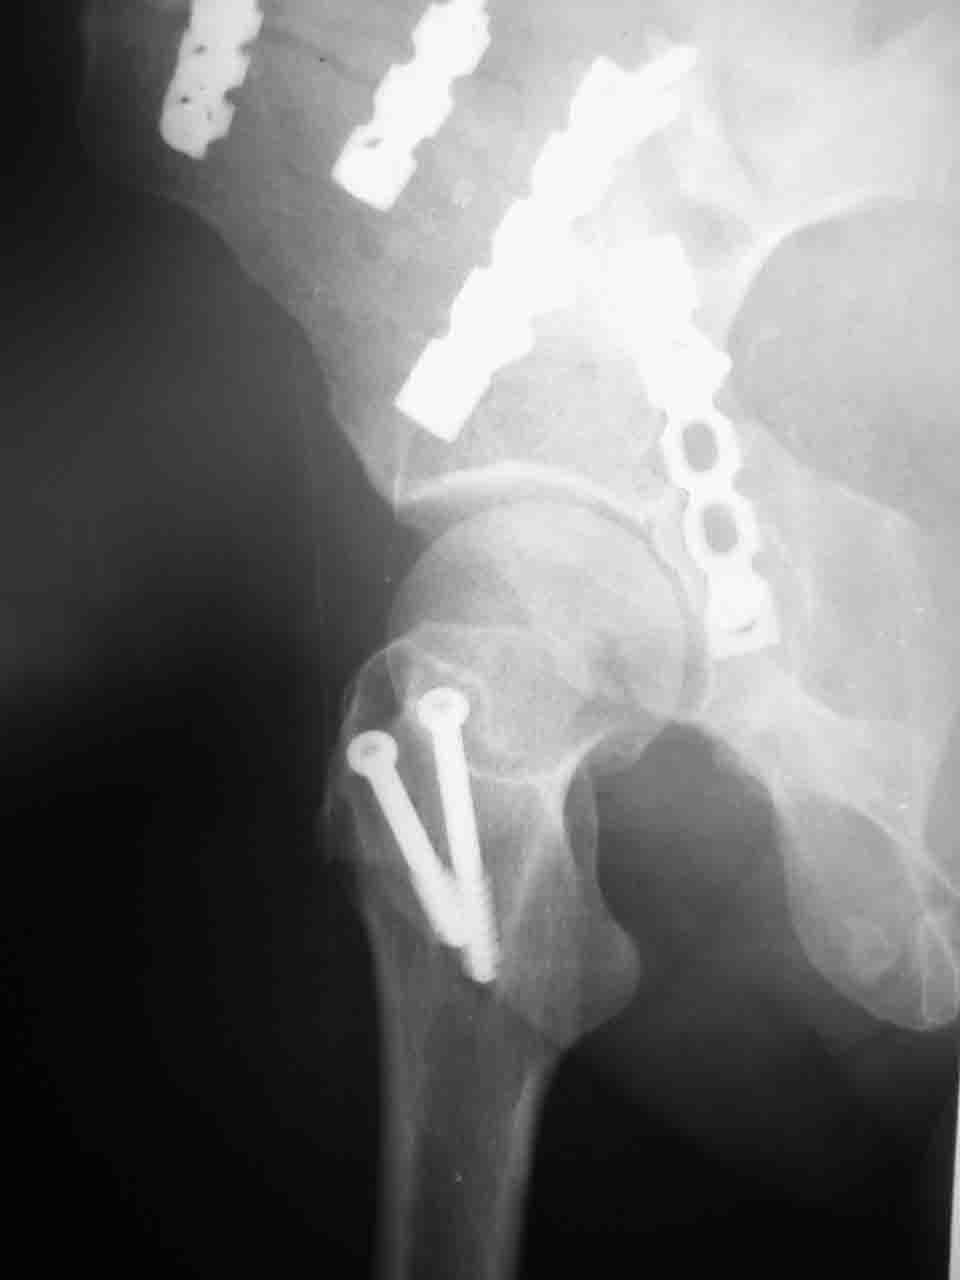

Снимки и схема